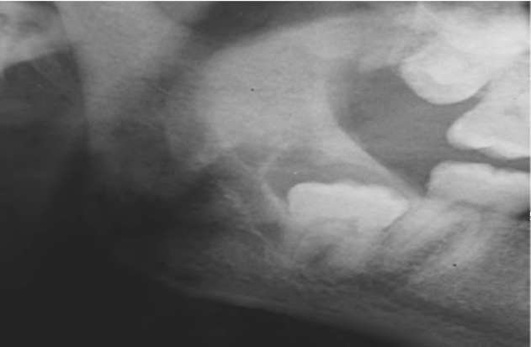

К локализованным формам хронического пародонтита относят поражения, охватывающие не более 30% площади пародонта. Причинами развития хронического локализованного пародонтита чаще всего являются местные факторы: аномалии прикрепления уздечек губ, языка и подслизистых соединительнотканных тяжей, мелкое преддверие полости рта, дефекты пломбирования зубов (отсутствие точечного контактного пункта и экватора зуба, нависающие края пломбы и т.д.), дефекты протезирования зубов и челюстей (широкий край коронки, длинная коронка, мостовидный протез большой протяженности, консольный протез, частичный съемный протез с плохой фиксацией и т.д.), дефекты ортодонтического лечения, аномалии положения и скученность зубов, нарушение прикуса и т.д. Эти факторы, воздействуя на пародонт длительный период времени, ведут к возникновению локализованного пародонтита или могут отягощать генерализованные формы пародонтита (рис. 14-19).

image

Рис. 14-19. Рентгенологическая картина хронического локализованного пародонтита